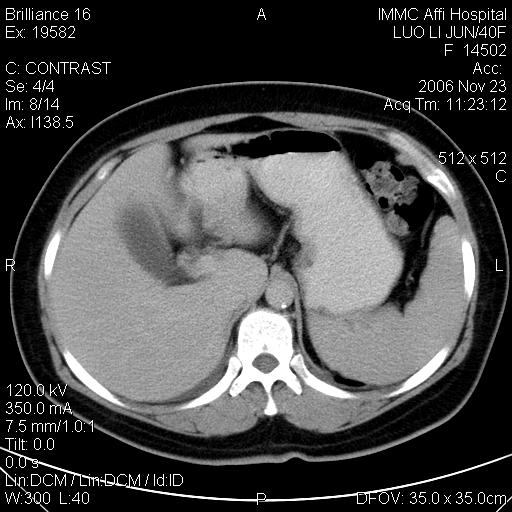

标题: CT5664:我也发一个肝脏的片子大家看看

很典型的肝癌。

典型肝癌

肝癌

速升速降,典型肝癌.

是啊,典型的早出早归!

快进快出典型肝癌.

快进快出,肝癌

符合肝癌的增强特征。支持肝癌!